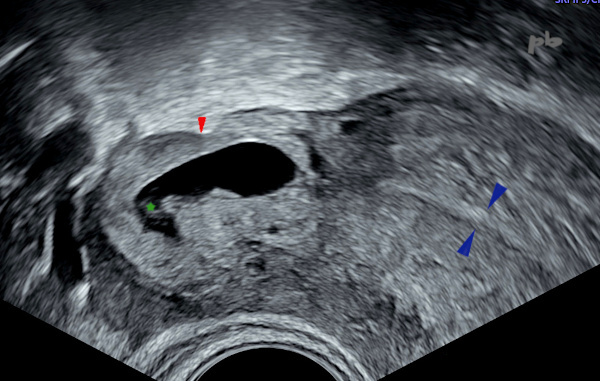

35- GEU interstitielle

- Sac gestationnel (►) contenant un embryon.

- Il est très excentré, an niveau de la corne utérine, avec persistance d’une bande de myomètre en périphérie de 2 mm.

- Le diagnostic différentiel peut être difficile avec un sac excentré, dans la corne utérine, mais restant endo-cavitaire.

35 – Interstitial pregnancy

Gestational sac (►) containing an embryo.

It is highly eccentric, at the level of the uterine horn, with persistence of a 2 mm band of myometrium at the periphery (between the crosses).

The differential diagnosis can be difficult with an eccentric sac, in the uterine horn, but remaining endocavitary.